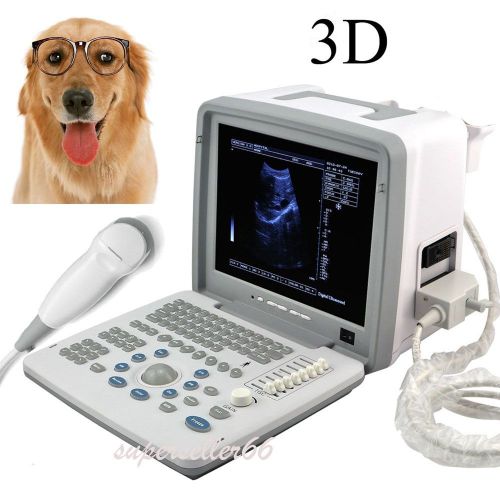

Model | 9000BV |

| Screen Size | 12 Inch | ||

| Image resolution | 800*600 | ||

| Probe | Rectal probe | ||

| Options | Linear / Convex / Micro-Convex |